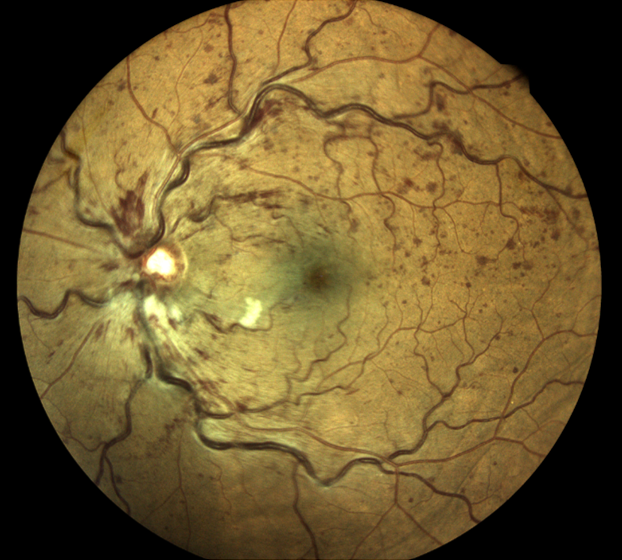

Rétinophotos couleurs montrant une occlusion de la veine centrale de la rétine, avec hémorragies en flammèches et des nodules cotonneux

Une occlusion veineuse rétinienne est un arrêt circulatoire partiel ou total d’une veine de la rétine, le plus souvent au niveau d’un croisement artério-veineu. Il peut toucher la veine centrale de la rétine ou une branche veineuse.

Le sang circule mal, la pression augmente en amont et cela provoque des hémorragies, un œdème et une souffrance rétinienne dans le territoire concerné.

Des rétinophotos couleurs permettent de visualiser la veine concernée par l’occlusion, la présence d’hémorragies intra rétiniennes, de nodules cotonneux etc … L’OCT objective la présence d’un œdème maculaire et de mesurer son épaisseur. Enfin c’est l’angiographie à la fluorescéine qui nous renseigne sur l’état de la circulation du sang dans les vaisseaux rétiniens et la présence de complications ischémiques périphériques.